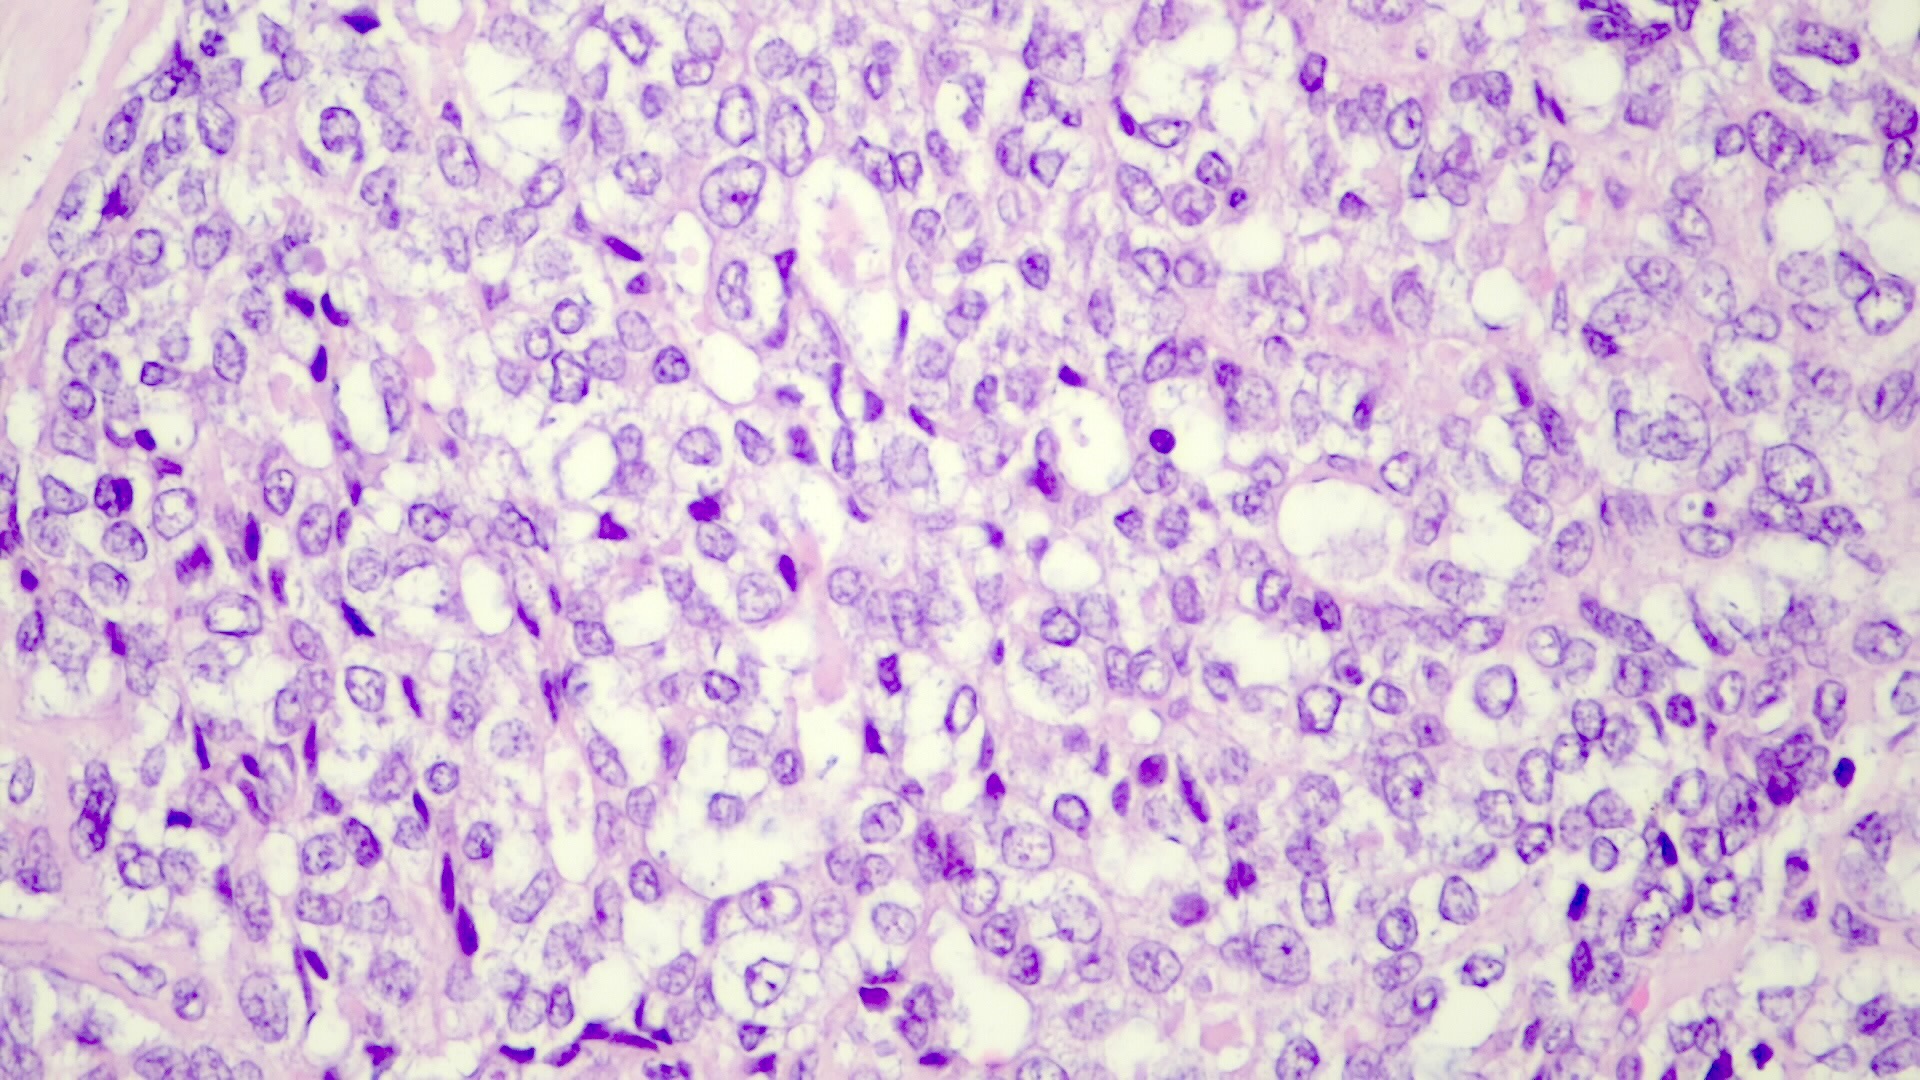

Macrotrabecular pattern (3%)

- Frequent trabeculae > 10 cells thick throughout the tumor, variable cytologic features

Small cell undifferentiated / anaplastic pattern (3%)

- Most primitive form

- Definition: 70%+ small cell areas; however, even small foci should be reported because associated with poor prognosis

- Discohesive sheets of small uniform keratin+ cells with minimal cytoplasm, indistinct cell borders, oval hyperchromatic nuclei, variable prominent nucleoli and increased mitotic figures (Mod Pathol 2003;16:930)

- Resembles small cell carcinoma at other sites

- May have mucoid stroma, hyalinized septae; bile

- Loss of INI1 associated with rhabdoid phenotype

- Small cell undifferentiated pattern (Pediatr Dev Pathol 2020;23:79)

- Solid sheets of discohesive small cells (small, round blue tumor)

- Abundant mitoses, apoptosis and necrosis

- Macrotrabecular pattern

- Thick trabeculae (5 - 12 cells thick)

- Trabeculae may be composed of fetal, embryonal, pleomorphic or hepatocellular carcinoma-like cells

Microscopic (histologic) images